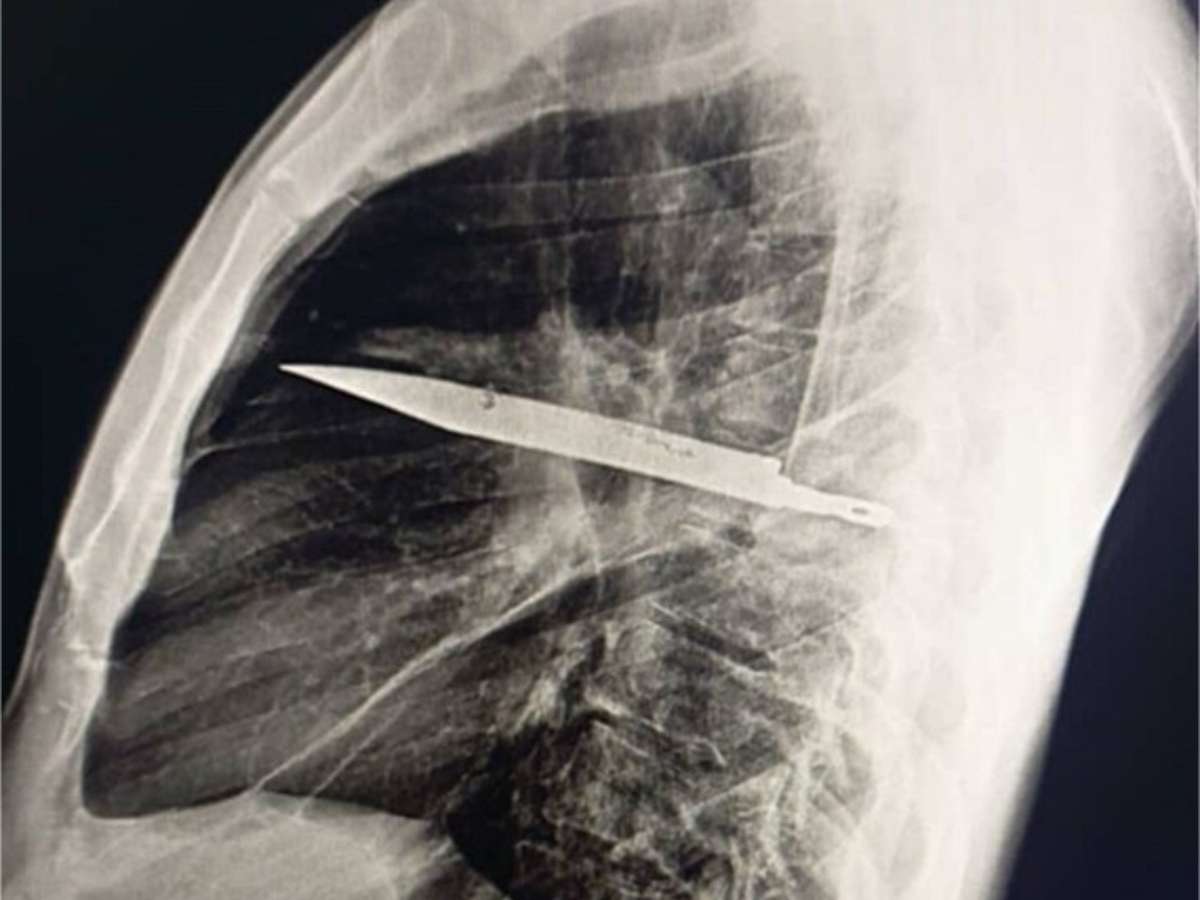

Foto: Reprodução/Biblioteca Nacional de Medicina dos Estados Unidos

Durante todos esses anos, o homem não apresentou sintomas. Somente quando a secreção surgiu é que procurou atendimento e os médicos decidiram realizar exames de imagem -- e a radiografia revelou a lâmina atravessada no peito, sem atingir órgãos vitais.